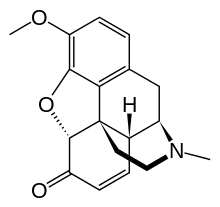

- Semi-synthetic opioids: created from either the natural opiates or morphine esters, such as hydromorphone, hydrocodone, oxycodone, oxymorphone, ethylmorphine and buprenorphine;